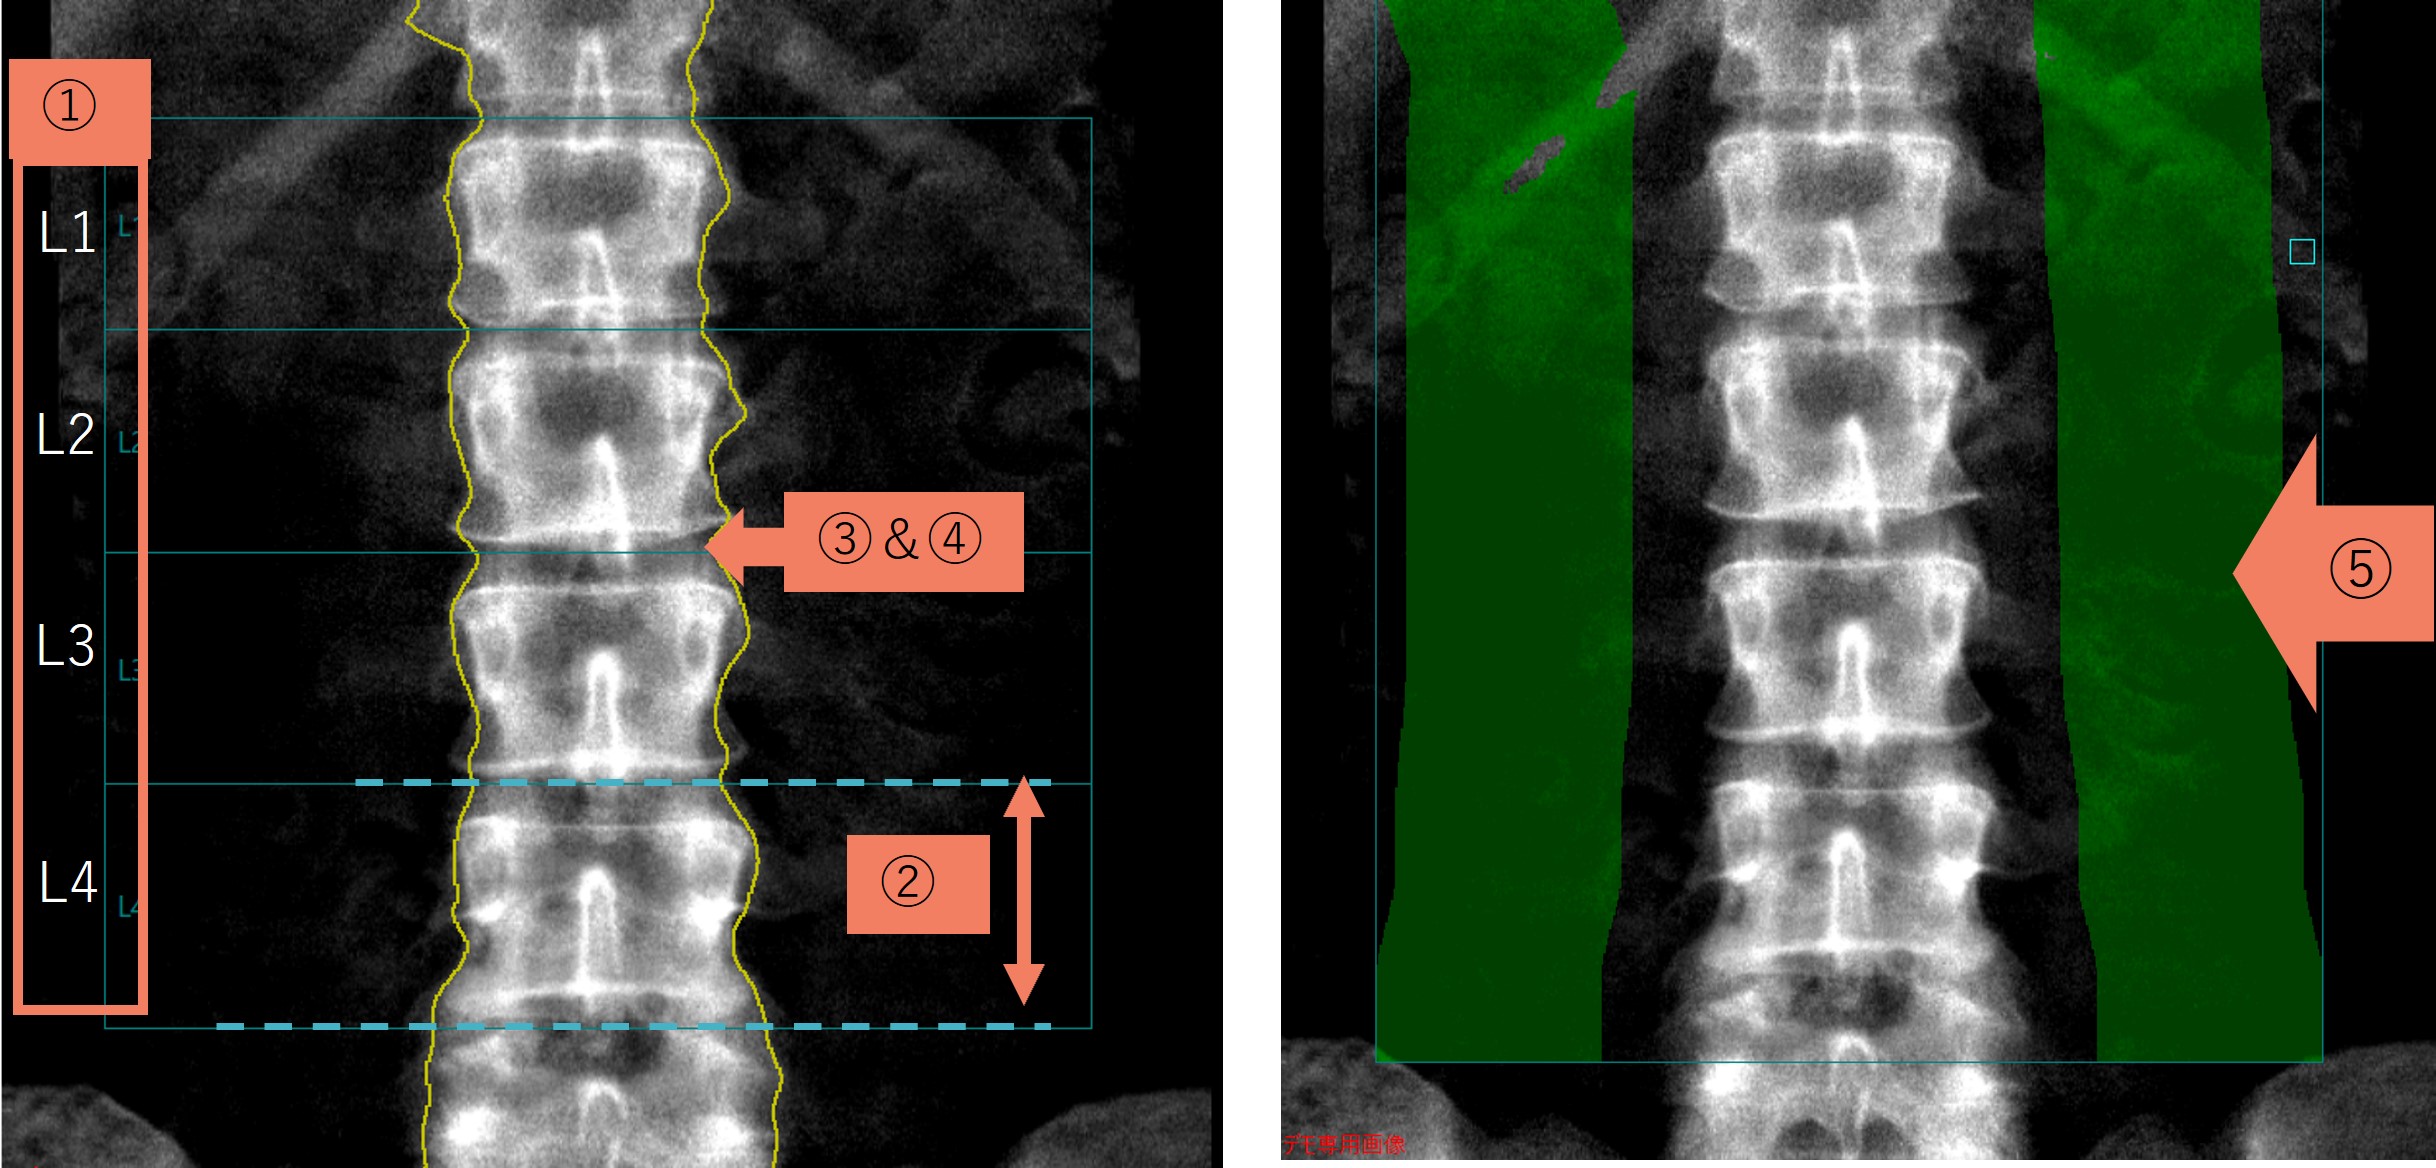

腰椎解析時の確認ポイント:下記①~⑤を確認してください。

Technical Tips_term03.jpg

①椎体の名前(L1等)があっているか?

②椎体の上下の線の位置及び角度があっているか?

③除外すべき椎体はあるか?

(特定の椎体の変形、骨折、石灰化が平均骨密度数値を押し上げてしまい、患者本来の数値を示していないと想定される場合など)

※骨硬化や圧迫骨折などで診断部位として不適切である場合は他部位(大腿骨など)での診断を推奨致します。

④適切な骨領域が囲まれているか?

⑤軟部組織の領域が適切かどうか?

※図はGEヘルスケア社DXA装置での理想的な軟部組織領域です。軟部組織の理想的な取り方はメーカーによって異なります。